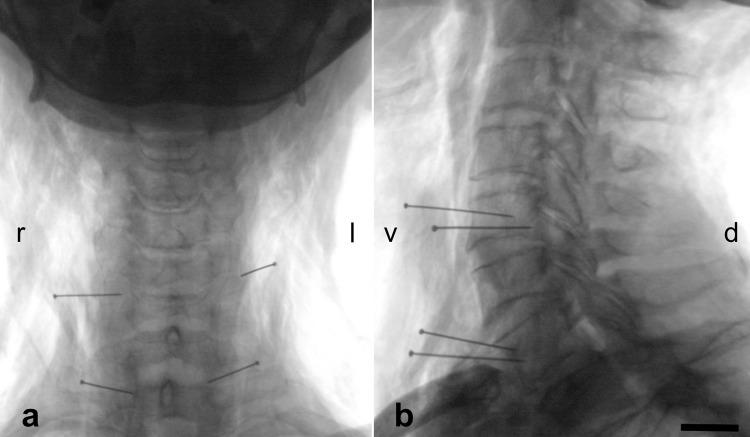

MATERIALS AND METHODS

Branching of the cervical vagus nerve was investigated macroscopically in 35 body donors (66 cervical sides) in the carotid sheath. After X-ray imaging for determining the vertebral levels of cervical vagus nerve branching, samples were removed to confirm histologically the nerve and to calculate cervical vagus nerve diameters and cross-sections.

在35具尸体供体(66个颈侧)的颈动脉鞘中宏观研究颈迷走神经的分支情况。在进行X射线成像以确定颈迷走神经分支的椎体水平后,取出样本进行组织学确认神经并计算颈迷走神经的直径和横截面积。